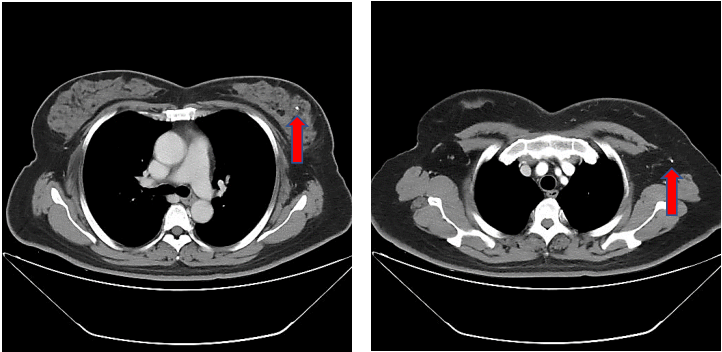

新辅助治疗6周期后再次CT评估,提示两肺未见明显异常密度影。纵隔内未见确切肿大淋巴结。双乳腺体致密,左乳局部可见点状高密度影,未见确切异常强化灶;双侧腋窝未见明显肿大淋巴结(图9)。

图9.新辅助治疗6周期后胸部CT平扫(箭头处提示金属clip位置)